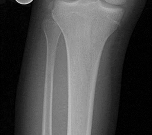

Question 11

A 9-year-old boy sustains a distal femur fracture. Radiographs demonstrate a fracture line propagating along the physis and exiting through the metaphysis, producing a small metaphyseal bone fragment (Thurston-Holland fragment). Based on the Salter-Harris classification, what type of fracture is this, and what is the typical expectation regarding growth arrest?

Explanation

A fracture that propagates through the physis and exits through the metaphysis (creating a Thurston-Holland fragment) is a Salter-Harris Type II fracture. It is the most common physeal fracture pattern. Because the germinal layers of the physis remain attached to the epiphysis, the general prognosis for growth is good. However, one must recognize that Type II fractures of the distal femur inherently carry a high risk of growth arrest (up to 40-50%) compared to other locations.